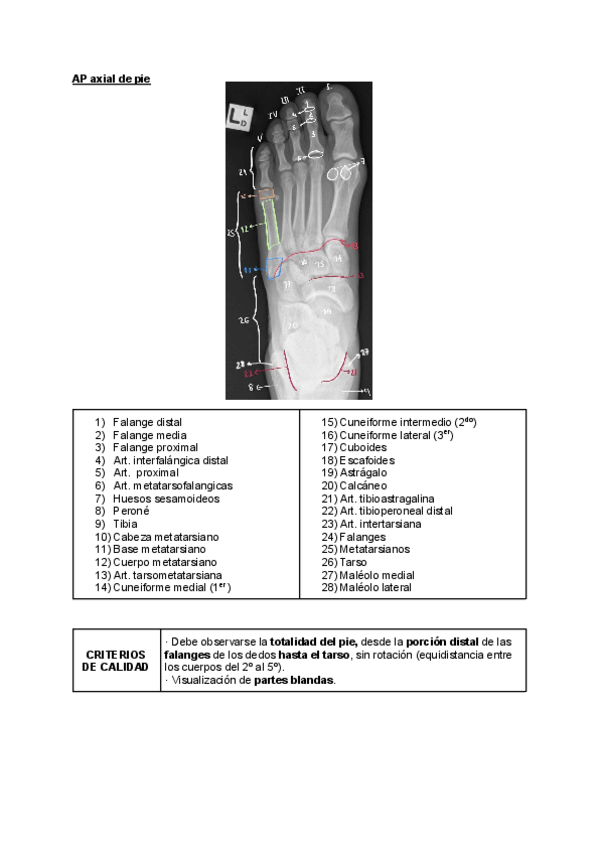

Radiología simple

He publicado nuevos trabajos de Técnicas de Radiología Simple: Radiología simple

Radiologia-Simple-Trabajo-Calidad-MIEMBRO-INFERIOR..pdf